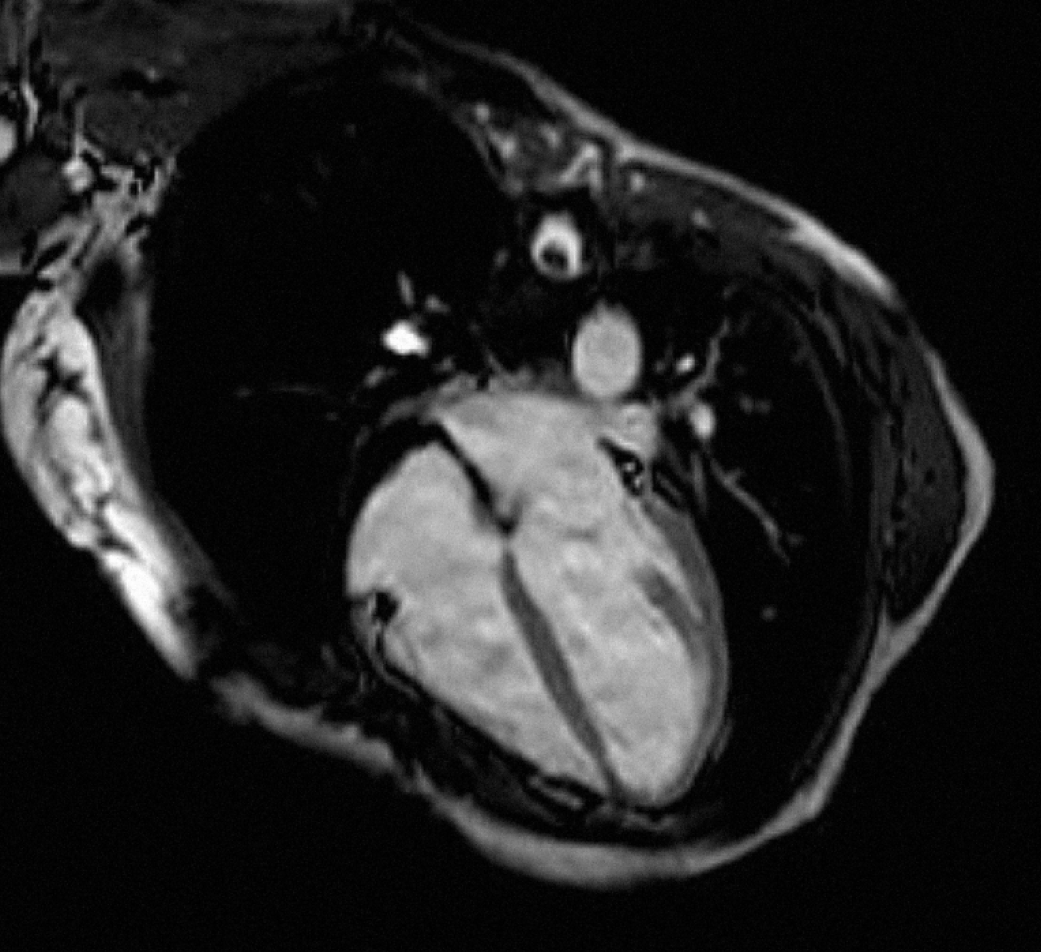

A 51-year-old Caucasian female with a past medical history of depression underwent dental procedure. She had no allergy, no history of smoking or alcohol consumption, and no family history of heart disease. The dentist injected a solution of 2% xylocaine into gum. Three minutes following the procedure, the patient complained for chest pain, during one hour. She was admitted to a cardiac intensive care unit. Her blood pressure was 125/65 mmHg, her pulse rate was 70 beats per minute (regular), and her spontaneous arterial oxygen saturation was 97%. Her physical examination was normal. Her electrocardiogram (ECG) revealed T waves inversions in AVF, DII, DIII, V4, V5 and V6 (Figure 1). Troponin level performed at admission was 23 ng/mL (N=0,05). C-reactive protein (CRP) concentration was normal. Chest X-ray was normal. Cardiac catheterization and ventriculography were normal. An early trans-thoracic echocardiogram and cardiac MRI found a global left ventricular hypokinesis with depressed ejection fraction of 40%, without late gadolinium enhancement (Figure 2)

(Figure 3) (Figure 4). Chest pain stopped the first day and the patient was discharged from hospital six days later, with beta blocker treatment (bisoprolol 5 mg/day). Left ventricular ejection fraction has been checked normal (65%) after five weeks of treatment. We concluded to atypical TTC induced by injection of xylocaine.